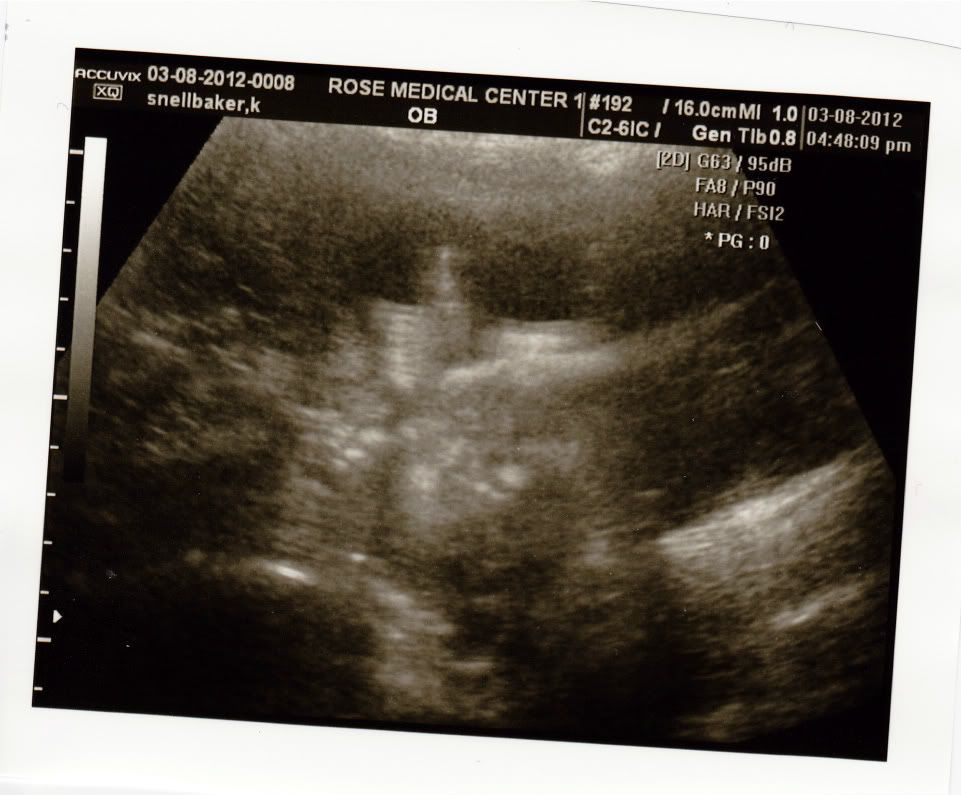

This is you moving your mouth and hands all around while we were watching!